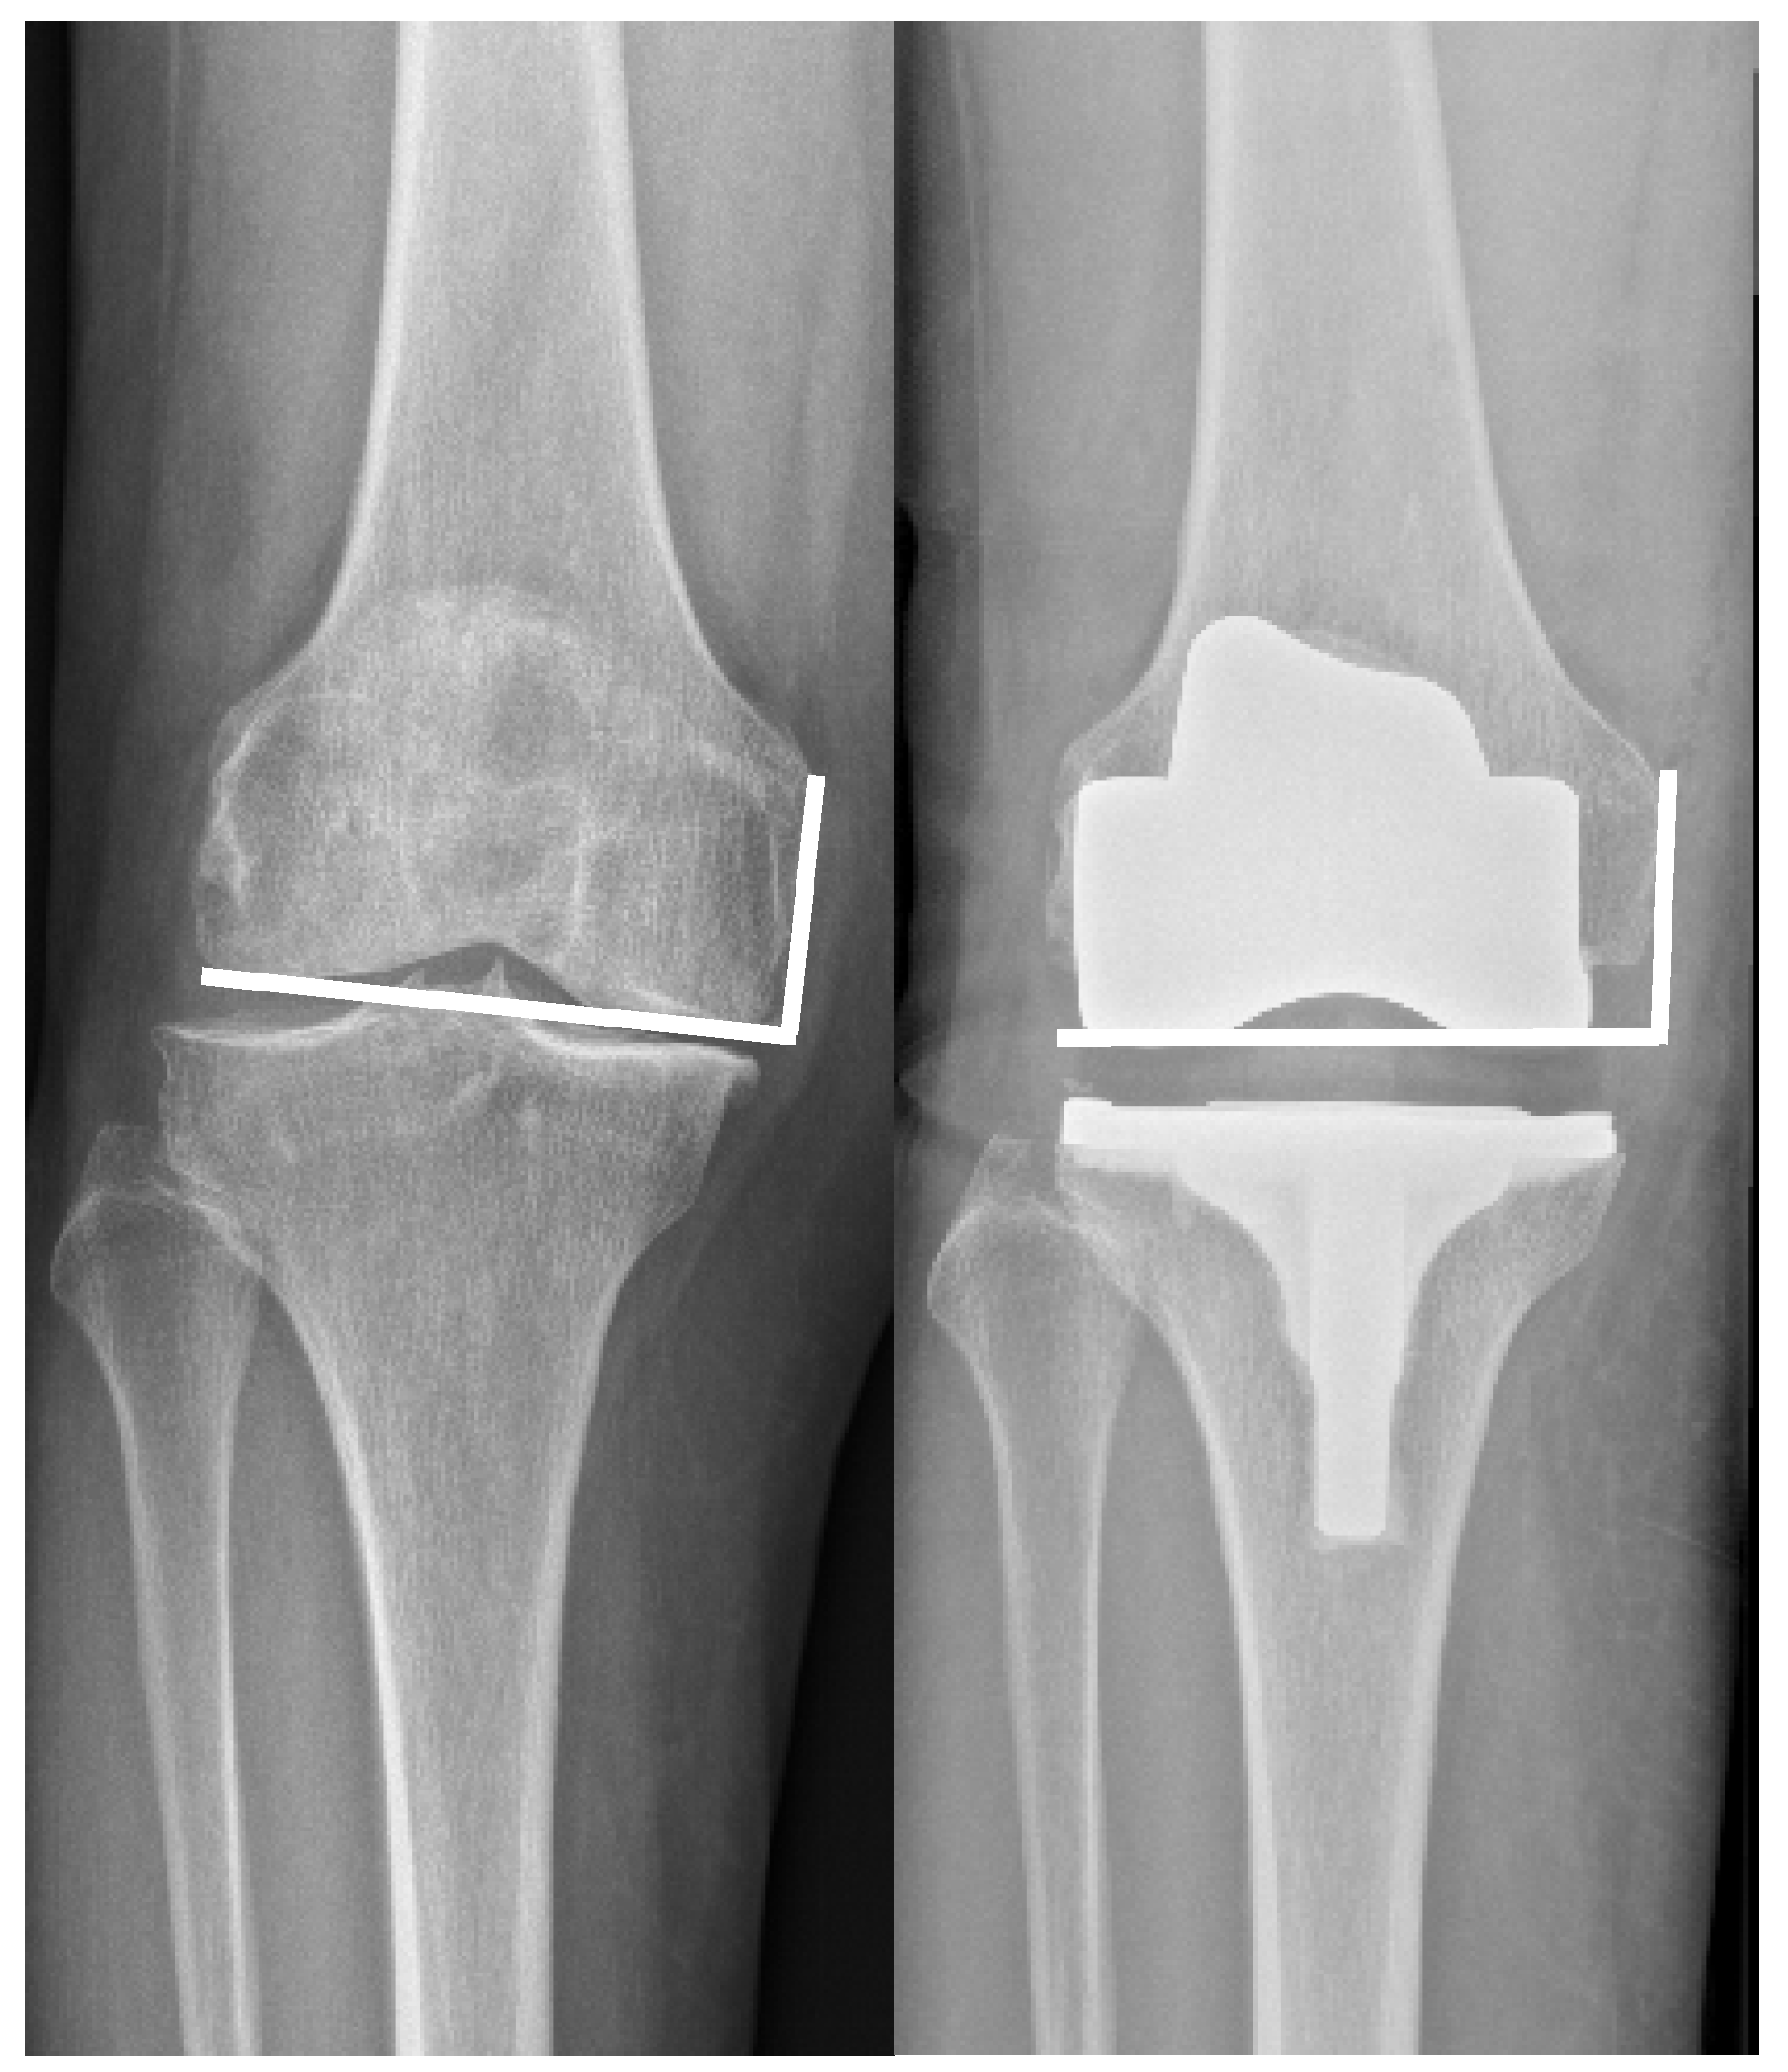

Influence of Mechanical Deformity on Joint Line Reconstruction

2. Materials and Methods